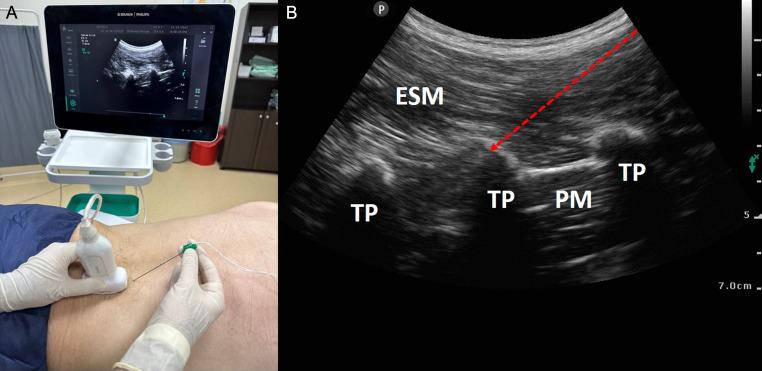

The sine qua non of enhanced recovery after surgery protocols designed to improve the perioperative experiences and outcomes of patients is to determine the most appropriate analgesia management. Although many regional techniques have been tried over the years in this purpose, interfacial plane blocks have become more popular with the introduction of ultrasound technology into daily practice and they have great potential to support effective postoperative pain management in many surgeries. The current article focuses on the benefits, techniques, indications, and complications of interfascial plane blocks applied in cardiac, abdominal, and spine surgeries.

旨在改善患者围手术期体验和结局的术后加速康复方案的关键在于确定最恰当的镇痛管理。尽管多年来为实现这一目的尝试了多种区域技术,但随着超声技术应用于日常实践,界面平面阻滞越来越受欢迎,并且在许多手术中具有支持有效术后疼痛管理的巨大潜力。本文重点关注在心脏、腹部和脊柱手术中应用的筋膜间平面阻滞的益处、技术、适应证及并发症。